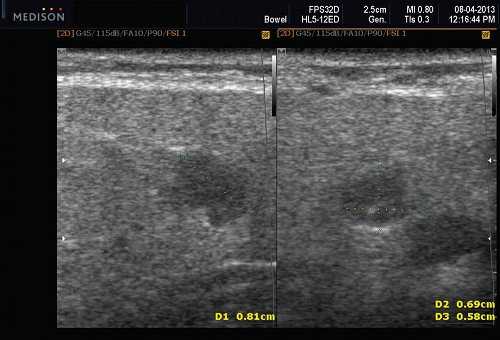

Рис. 3. Сиаладенит правой поднижнечелюстной слюнной железы.

Рис. 5. Камень протока поднижнечелюстной слюнной железы.

Рис. 6. Камень в паренхиме поднижнечелюстной слюнной железы.

Рис. 7. Камень в протоке поднижнечелюстной слюнной железы.